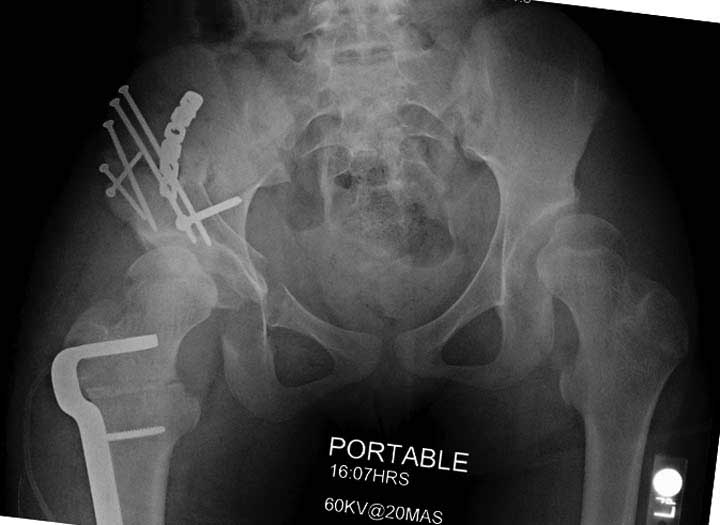

Жалобы на двухсторонние постоянные боли при нагрузке и неустойчивость. Внутренная ротация конечности в суставе более 40 градусов и на рентгенограмме двухсторонний подвывих головки с нарушением линии Шентона, а на боковом снимке с минусовым покрытием головки. МРТ - удлиненная связка и импинджмент (бугор) в шейке.

Первым этапом сделана подготовка к ротационной межвертельной остеотомии, затем капсулотомия с удалением импинджмента и периацетабулярная остеотомия с 40 градусной экстензией и операция закончена 35 градусной наружной ротацией бедра. Запланированный варус не сделан из-за относительно нормального покрытия головки.

Одним из преимуществ ПАО является сохранение задней колонны, и всю фиксацию в основном делают спереди из крыла подвздошной кости. При реконструкционных операциях по поводу дисплазии редко коррекция превышает 25 градусов, и достаточной бывает фиксация тремя шурупами вертикально сверху вниз, и один между колоннами спереди кзади. Но у нашего пациента серьезные изменения, и для достижения результата надо было около 40 градусов коррекции, из-за чего в линии остеотомии создалась ступенька. Для предупреждения скольжения дополнительно установлена buttress пластина, которая зафиксирована только в одном сегменте, а другие два шурупа удерживают ASIS. Без остеотомии Anterior Superior Iliac Spine невозможен доступ внутри таза.